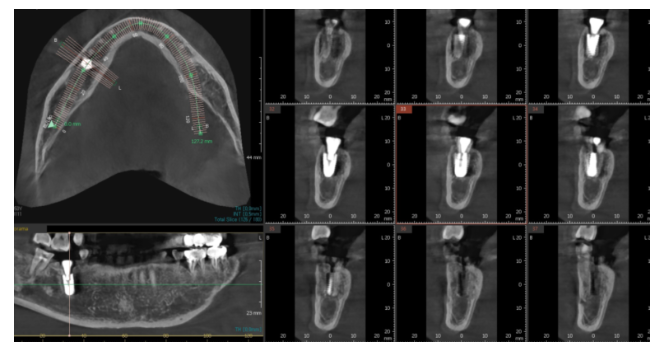

231023

강동구 치과 임플란트 식립한 사진입니다.

투석을 하지 않는 날 수술을 시행했고

수술 전 예방적 항생제 복용으로 감염 위험 최소화

수술 후 매일 전화를 드렸습니다.